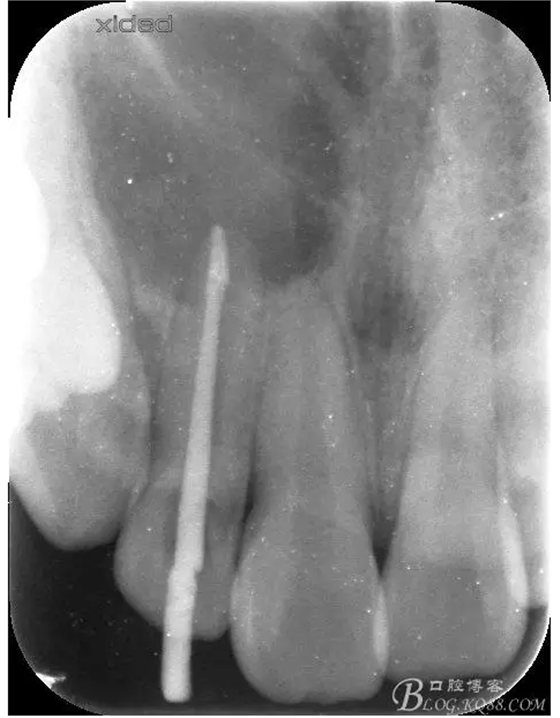

1.術(shù)前的根尖片檢查及根管治療影像:

圖3.依缺損部位為中心,逐漸去骨,完整暴露出囊壁。

圖4.摘除囊壁后形成的巨大骨腔